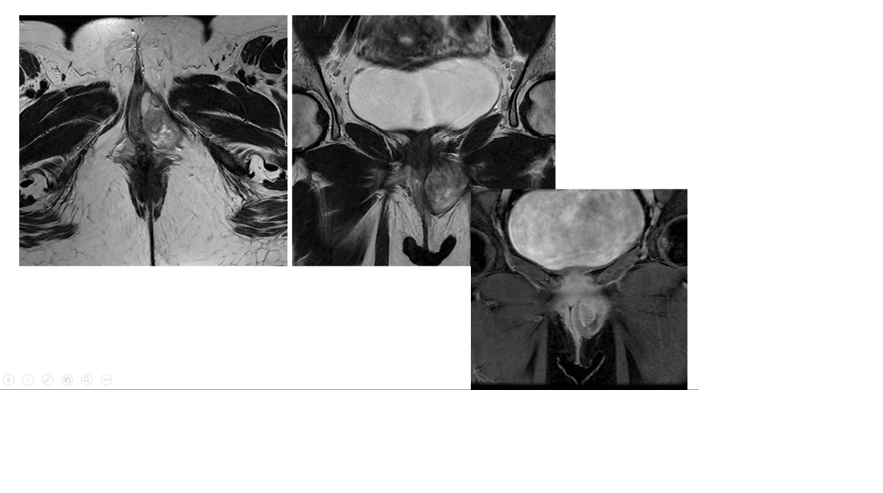

Histopathology from the first surgery suggested aggressive angiomyxoma based on the spindle cell tumor’s morphology. However, the diagnosis was inconclusive due to incomplete excision. An MRI in August 2024 revealed Left pelvic mass measuring 5 x 3 x 4 cm. Show bright T2 signal intensity with a swirling appearance crossing the left levator ani muscle towards the left external anal sphincter abutting the sphincter. Internal sphincter and intersphincteric fat are intact. Mass extends to the left vaginal wall with an indentation of the vaginal wall at the level of the urethra. The mass shows avid enhancement post-contrast (Figure-1).

Ultrasound (US) is the primary imaging technique used to evaluate vaginal masses due to its high resolution, availability, and cost-effectiveness. It can distinguish between vulvar and vaginal amyloid-beta (AMFB) and other mesenchymal tumors.[11]. AMFB is typically well-circumscribed on MRI and is often described as hypointense on T1W images, hyperintense on T2W images, and with homogenous hyperenhancement on Gd-C enhanced images. Contrast-enhanced imaging has been reported in five studies [11]. Regarding our case, the initial MRI suggested angiomyxoma or myxoid liposarcoma as possible differentials. After the first excision surgery, MRI shows bright T2 signal intensity with a swirling appearance crossing the left levator ani muscle towards the left external anal sphincter abutting the sphincter.

Figure 1. Preoperative MRI showed left pelvic mass measuring 5 x 3 x 4 cm. Show bright T2 signal intensity with a swirling appearance crossing the left levator ani muscle towards the left external anal sphincter abutting the sphincter.